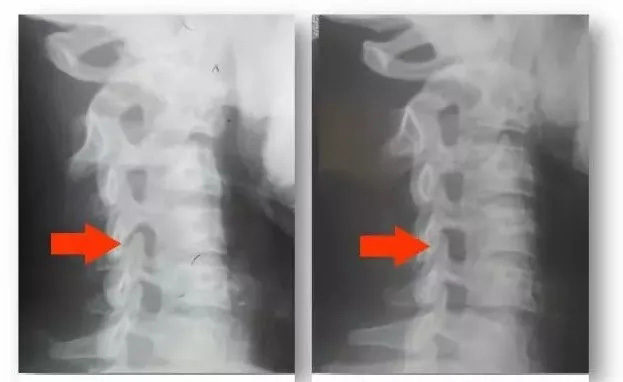

误区之二:骨质增生是颈椎病的罪魁祸首“骨质增生”又叫“骨刺”、“骨赘”,看到“刺”这个字,总是会给人带来一种不愉快的联想!到了一定年龄去医院拍片子,诊断报告中常常会看到这样的描述,此时不单单是不愉快,有时会很担心,甚至是恐惧,因为很多人都说骨刺会扎到神经,弄得不好还要开刀把骨刺割掉。

随着年龄的增大,一天天变老,我们身体的内部在不知不觉中发生着一系列的变化,医学上叫做退化,或是退行性变,这是一种正常的生理现象,通俗地说就是老化。 试想一位五、六十岁的人皮肤还像二十来岁一样光滑润泽,那不成怪物了吗?身体表面的变化我们随时能够看到,例如皮肤脱水干燥了,进而慢慢有皱纹和老人斑了,但藏在身体里面的骨头也在同步发生着类似的变化,像骨质增生、骨赘、骨刺、椎间盘脱水或膨出等等这些医学上的描述,说的都是“退化”现象,他并不等于疾病,在大多数情况下,骨头的退化程度与临床症状之间并没有直接的关系。

相反,骨质增生是因为人体自身的需要才长出来的。在退化比较快或劳损强度比较大的一段时间里,关节的稳定性会下降,如果用手术的方法治疗,会放入一块儿人工 钢板来进行加固,这是一种起效比较快的“霸道”的治疗方法;如果能够坚持到骨质增生慢慢长好,也同样能够重建关节的稳定,只是需要的时间长一些,因此是一 种“王道”的方法。在这个过程中,也可能因为骨刺长的位置不好刺激到周围的神经、血管等而引起临床症状。

骨质增生对于重建关节稳定是十分有利的,他就好比身体自己长出来的“钢板”,因此,我们要善待他,不到万不得已千万别轻易“除掉”他,反而要与他交朋友,通过适当的活动去主动适应他,与他和平共处,这样便会相安无事,共筑和谐。